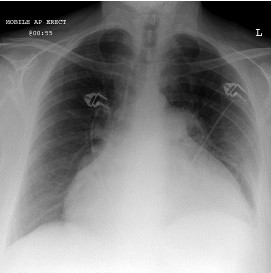

Mulher de 50 anos chega à Emergência com queixa de dispneia e desconforto torácico. Apresenta história de dor torácica intensa, manejada em hospital do interior como infarto do miocárdio sem estratificação invasiva, há uma semana. A paciente apresenta PA 90/40mmHg, FC 120mmHg, turgência venosa central e mínimos estertores crepitantes em bases; está fria e com sensório deprimido. RX de tórax (Fig. 1) e ECG (Fig. 2) da chegada estão representados abaixo.

Fig. 1